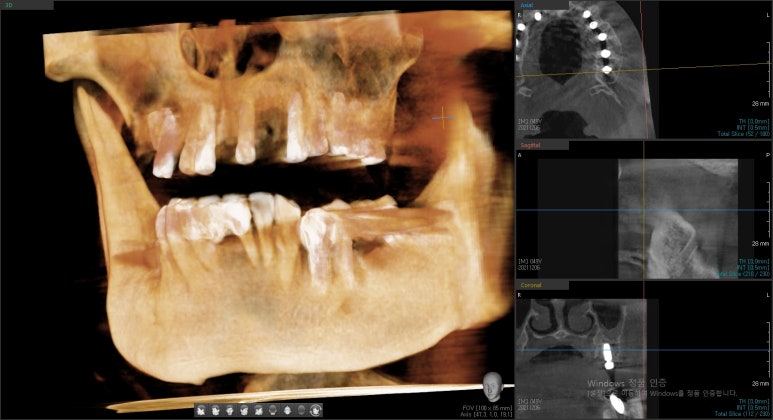

네비게이션 임플란트를 사용하여 적절한 간격과 각도를 유지하였고

특히 앞니의 경우 뼈가 매우 얇았으나 내비게이션을 사용하여

뼈가 얇아도 뼈를 뚫고 나갈 위험이 없이 적절한 뼈 위치에 임플란트를 식립하였습니다.